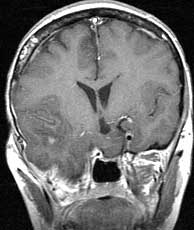

T1 coronals post gad

Findings:

Herniation of the right temporal lobe into the infratemporal fossa with no abnormal enhancement. A few scattered foci of increased signal unchanged compared to pre-gad coronals.